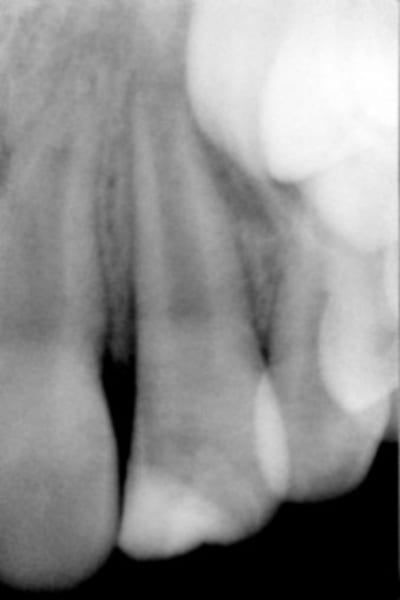

gamin 8 ans, fils d'un couple d'amis. fracture à l'école: compo+ surveillance: contrôle à 2 mois: dent ne répond pas aux tests de vitalité, y compris les coups de casserole.

Controle radio pour voir si édification radiculaire, si pas bon apéxification avec Ca(OH)2

voici une radio.

As-tu une radio à j 0 pour voir si il y a eu une évolution ?

Une vitalité pulpaire ça peut mettre un an à revenir, mais tes douleurs à la percussion (c'est bien ça ?) pourraient évoquer une nécrose, avec résorption inflammatoire à suivre.

c'est vrai que je n'ai pas vraiment fait un tableau clinique complet, donc:

-fracture amélo-detinaire sans effraction

- à 2 mois, changement de coloration, mobilité persistante mais atténuée, douleur légère à la percussion. tests négatifs.

Attention, lorsque l'apex n'est pas fermé les tests de vitalité sont négatif,donc la dent peut être encore vitale.

l'objectif primordial je crois est d'avoir un apex

faut temporiser et comparer les rd dans le temps

quand l'apex sera fermé toutes les possibilités seront ouvertes